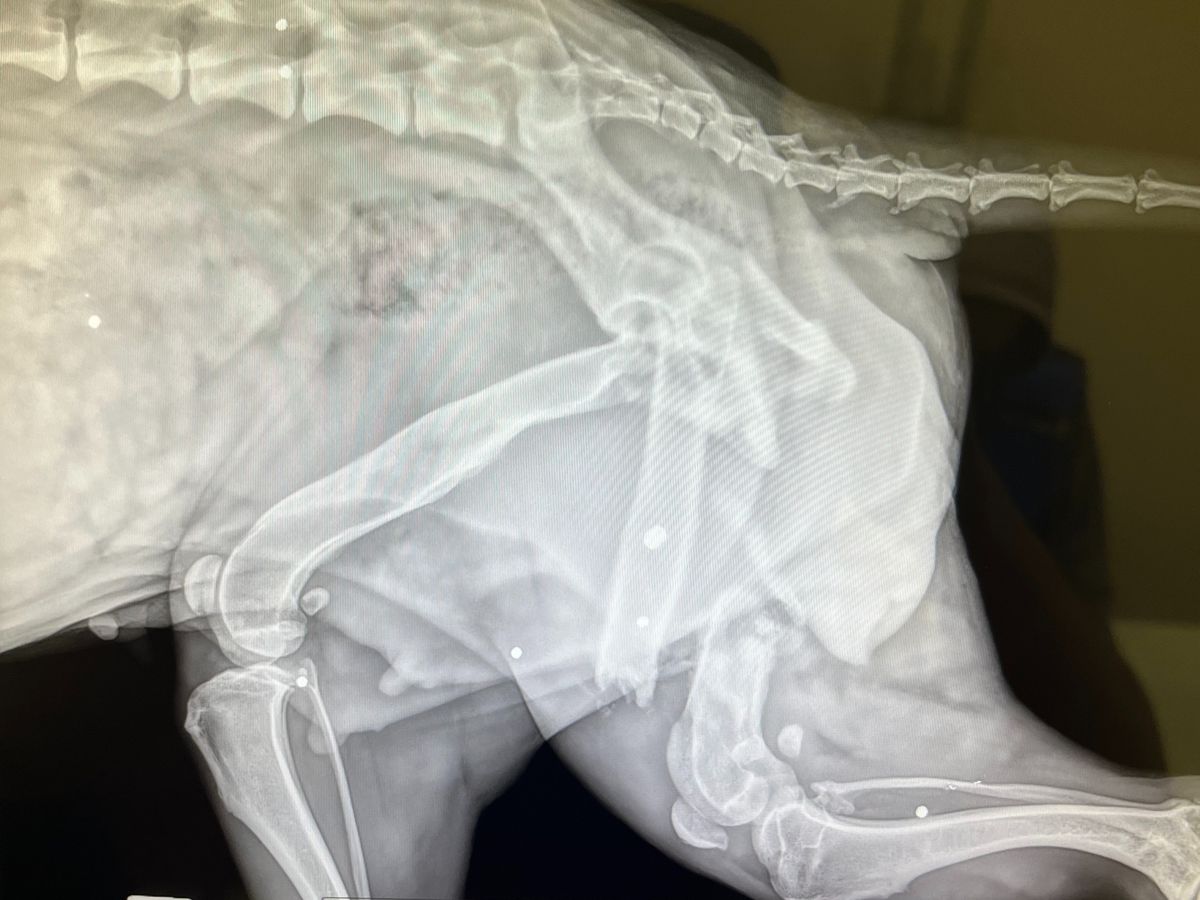

With the help of Dr. Andrew Atuan, a local Atlanta vet, we were able to get them cleaned up, medicated, and stabilized. But as the days passed, it became clear that Roxy wasn’t healing—she struggled to walk and carried a painful limp. X-rays revealed the heartbreaking truth: her femur is completely broken, and she carries the scars of multiple gunshot wounds. It is nothing short of a miracle that she is alive and even more incredible that, through it all, she never stopped protecting and caring for her puppy, Milo.